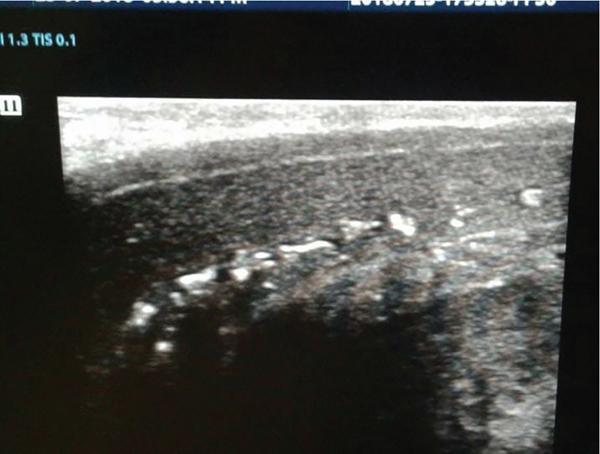

Rijo Mathew Choorakuttil The penis is a superficial, protruding organ that is highly vascularized and composed of several soft tissue structures. Penile pathologies and abnormalities are not uncommon, although they are not usually as well discussed as other organ pathologies. Ultrasound studies are useful in the assessment of penile pathologies and dysfunctions. In this chapter, you will learn about Penile erection is primarily a neurovascular phenomenon, initiated by erection triggers such as imagination, visual, auditory, olfactory, genital and nongenital tactile stimulation. These triggers result in neurologic signals transmitted through the parasympathetic nerves and release of nerve-derived nitric oxide (nNOs) and vasodilatation. Due to the vasodilatation, endothelium-derived nitric oxide (eNOs) is produced, which continues to produce vasodilatation if the erection triggers are continuously operating and facilitated only in the presence of a hormonal and psychological environment. Sexual stimulation initiates the release of neurotransmitters from the cavernous nerve terminals and relaxing factors from the endothelial cells result in arteriolar smooth muscle relaxation. Increased blood flow and relaxation of the cavernous smooth muscle result in rapid filling and enlargement of sinusoids against the TA. The compression of the subtunical venular plexuses lead to a significant occlusion of venous outflow. Blood is trapped within the cavernosa and raises the intracavernosal pressure (ICP). This leads to full erection. The base of the corpus cavernosum, which is blood filled, is compressed by the ischiocavernosus muscle during sexual activity. The penis enters the rigid erection phase with temporary cessation of the inflow and outflow. Emissary veins get contracted between the circular and oblique fibres of tunica to maintain the blood filled in sinusoids in erection. Detumescence begins as the trabecular smooth muscle contracts and venous channels open, expel the trapped blood and restore flaccidity. The penis is an organ given to intermittent tumescence that is often related to sexual stimulation. Priapism is a persistent tumescence unrelated to sexual stimulation that usually lasts more than 4 h. Priapism can be categorized as arterial and venous types. Arterial priapism is less common that venous or ischemic priapism. Ischemic priapism, caused by decreased or absent venous drainage is a medical emergency that needs immediate attention. Arterial or high-flow priapism is often seen in fistula formation or cavernosal metastasis of a solid tumour and is caused by arterial influx that is increased and often uncontrolled. Arterial-lacunar fistula seen in arterial priapism may directly extend to the cavernosal tissue and bypass the helicine arteries. Colour Doppler ultrasound (CDUS) studies reveal a characteristic colour blush and turbulent high-velocity flow. Low-flow or ischaemic priapism occurs as a failure of tumescence characterized by the absence of cavernosal blood flow. Low-flow priapism commonly reveal a lack of CA blood flow or with a very high-resistance flow pattern in the CA in CDUS. Progressive curvature and shortening of the penile shaft are the characteristic of Peyronie’s disease. It may be associated with a palpable nodule and may lead to pain during erection and dyspareunia. Penile ultrasound imaging studies may show multiple calcified nodules along the tunical envelope of the cavernosum and signs of veno-occlusive erectile dysfunction (ED) (Fig. 11.13.1). Improvements in real time spatial resolutions and contrast have helped in the preoperative assessment of Peyronie’s disease and the quantification of penile fibrosis. Sonoelastography and contrast-enhanced penile ultrasound studies can also help to provide more information on penile pathology. Sonoelastography techniques are useful to differentiate and detect noncalcified fibrous plaques. ED may be psychogenic, organic or of mixed aetiology. Reliable estimates on the exact prevalence of ED is scarce, although some studies have reported a prevalence of 12% in men aged above 18 years and 25%–30% in men aged between 60 and 70 years and 52% in the Massachusetts Male Aging Study. Nearly 70% of men may suffer from ED at some time during their life and 30% of men may experience one episode of ED in a given month. Estimates suggest that an estimated 152 million men worldwide were present with ED in 1995 and this may increase to nearly 322 million men with ED by 2025. ED can cause stress, affect self-image and cause lack of confidence as well as relationship problems. ED can also suggest an underlying health condition that needs treatment. ED is one of the earliest manifestations of endothelial dysfunction and peripheral vascular and cardiovascular disease in men. Vascular insufficiency and ED secondary to excessive venous leakage is the most common cause of organic ED. Persons with ED of vascular causes have more markedly impaired endothelial and smooth muscle functions compared with patients having similar risk factors but no ED. The prevalence of vascular comorbidities increased with ED severity suggesting that ED may be a prognostic marker for overall health. ED is an important legal question especially in cases or marital consummation, separation and divorce and rape and sexual assault. Doppler ultrasound studies may be useful in the determination of ED in such cases. The treatment of structural penile diseases depends on the underlying causes. Medical therapy may help in patients with moderate disease while surgical correction may be needed for persons with severe penile deformity. It is possible to minimize the diagnosis of indeterminate cause with proper ultrasound techniques and interpretations. The determination of psychogenic ED is important and appropriate counselling and psychotherapeutic processes may help to alleviate symptoms in psychogenic ED. Penile trauma is relatively rare, but not uncommon and has a reported incidence of 1 in 175,000 hospital admissions. Rupture of the TA and the corpus cavernosa, often seen in the setting of an erect penis during vigorous sex, direct trauma, masturbation, falls, forceful manipulation and rolling over in bed during an erection, can lead to penile fractures (PF). PF may need emergency surgical repair. On the other hand, blunt penile injury without disruption of the TA or urethral injury may be treated conservatively. The TA, which has a normal thickness of 2 mm in a flaccid penile state elongates during erection with a reduction of thickness to 0.25 mm. A transverse rupture of the corpus cavernosum can lead to a curved or bent penis. Penile fracture generally occurs in the proximal or middle shaft and results in a transversal tear. Radiologic evaluation for PF includes retrograde urethrography, cavernosography, magnetic resonance imaging (MRI), US and CD ultrasonography. Retrograde urethrography and cavernosography are invasive and with high rates of false-negative findings. MRI is an excellent imaging modality with multiplanar capability and excellent tissue contrast but is expensive and not widely available everywhere. US is ideal to evaluate patients with penile trauma and can be routinely used in an emergency. It is a noninvasive method and should be performed with a high-frequency (7–12 MHz) linear transducer, anatomic orientation and ample gel to provide high-quality images. Ultrasound studies that use high-resolution greyscale imaging, high-frequency broadband traducers, in isolation or with colour and pulsed-wave Doppler are the initial tests for the evaluation of penile trauma. Colour duplex Doppler ultrasound (CDDU) is performed using a high-resolution probe – range of 10 to 16 MHz positioning the probe at the crus (at the level of penoscrotal junction) and at mid penis (1/2 distance between the penoscrotal junction and the coronal sulcus). Vasoactive drugs (intracavernosal injection of papaverine 60 mg (n = 700) or prostaglandin E-1 20 mcg, n = 1576), audiovisual sexual stimulation (AVSS) and/or tactile sexual stimulation (TSS), in a quiet room with aesthetic and erotic environment and without any external disturbances are part of the assessments as appropriate. The assessments are done in the presence of a team that included andrologist, radiologist and sex therapist. Sampling factors, gate placement and angle corrections are optimized for consistent, reproducible results. The penis is scanned from its ventral surface using longitudinal and transverse views. Evaluation is done with the penis in a flaccid state and after the intravenous injection of the vasoactive drugs. CDUS with spectrum analysis is performed with tuning for a slow-flow setting. Penile bodies present with intermediate echogenicity and homogeneous echotexture in the flaccid state. After a cavernosal injection, sinusoidal distension begins in the central portion of the cavernosa and is less echogenic than the outer portion. The filling phase reveals several fine echogenic grids of the sinusoidal interfaces in the corpus cavernosum. The penile septum is a back attenuated echogenic structure that may obstruct the evaluation of the dorsal penis and the TA. The sampling location and angle can influence the measurement of the peak systolic velocity (PSV) of the CA (Fig. 11.13.2). Colour Doppler signals are used to guide spectral sampling of the CA at the origin on the base of the penis, at the site where CA angles posteriorly toward the crus. This helps to standardize velocity measurements. It is preferable to apply the angle correction cursor or the steering box (Fig. 11.13.3).